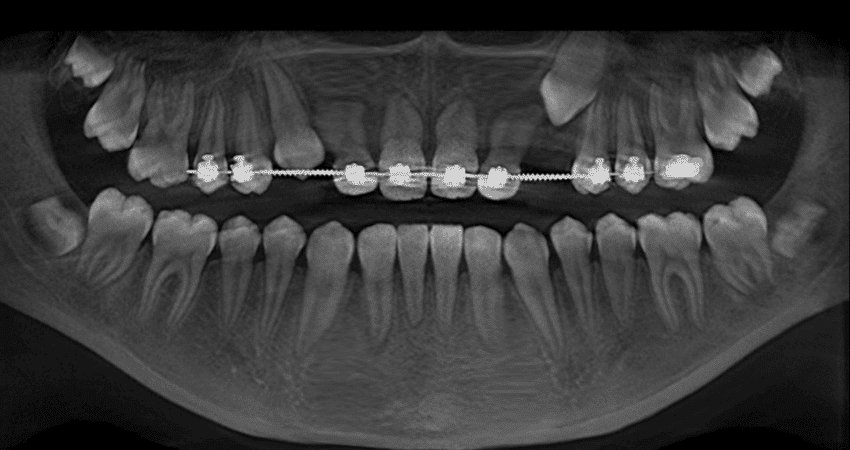

Ortodonzia

In alcuni casi, il trattamento ortodontico può essere necessario per correggere la malocclusione causata dalla microdonzia. Gli apparecchi ortodontici possono aiutare a riallineare i denti e a chiudere gli spazi tra di essi.